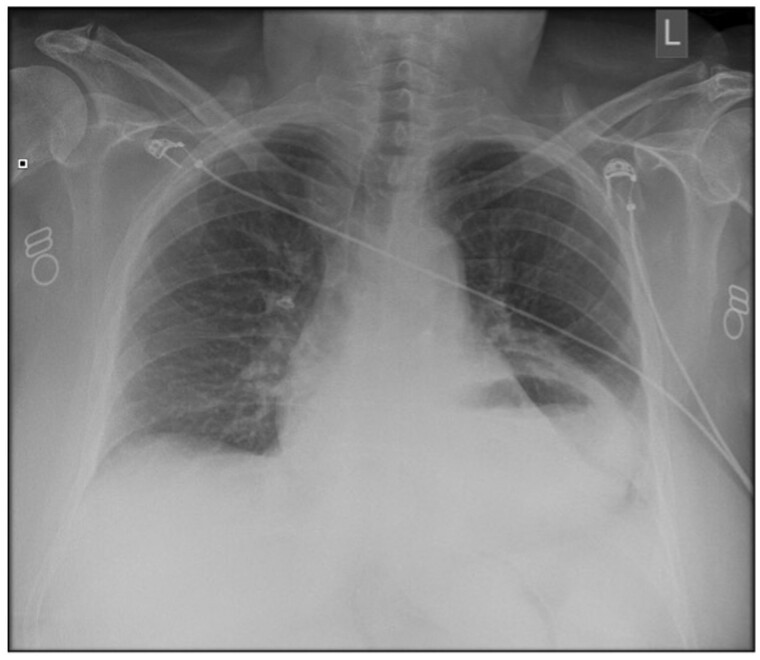

Gastric pneumatosis is a rare finding, and clinicians, when under pressure, find it challenging to immediately identify the cause and decide if the patient requires emergency surgery. We present a case where an initial CT scan demonstrated gastric pneumatosis involving only the greater curvature of the antrum caused by a strangulated hiatus hernia and malrotation of the distal stomach. The CT features suggested the patient required immediate surgery; however, a conservative approach was taken, and a follow-up CT scan 4 days after the onset demonstrated complete resolution and no long-term complications.